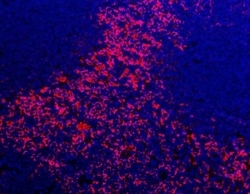

RQ8384 IHC

Full details

Method:

Other validation